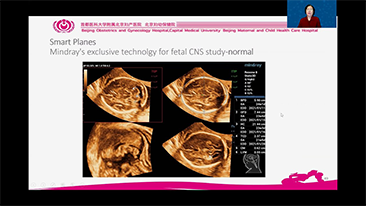

L'ottimizzazione dei flussi di lavoro in ambito ostetrico e ginecologico ├© necessaria per completare grandi volumi di visite di screening per la salute delle donne. Ad esempio, le malformazioni del sistema nervoso centrale (SNC) sono una delle anomalie congenite pi├╣ comuni. A causa di varie circostanze che limitano l'accuratezza delle immagini, come la posizione poco adeguata del feto, l'MSP ├© particolarmente difficile da rilevare tramite l'ecografia 2D. Pertanto, il rilevamento e le misurazioni automatizzate possono migliorare notevolmente l'efficienza della scansione.